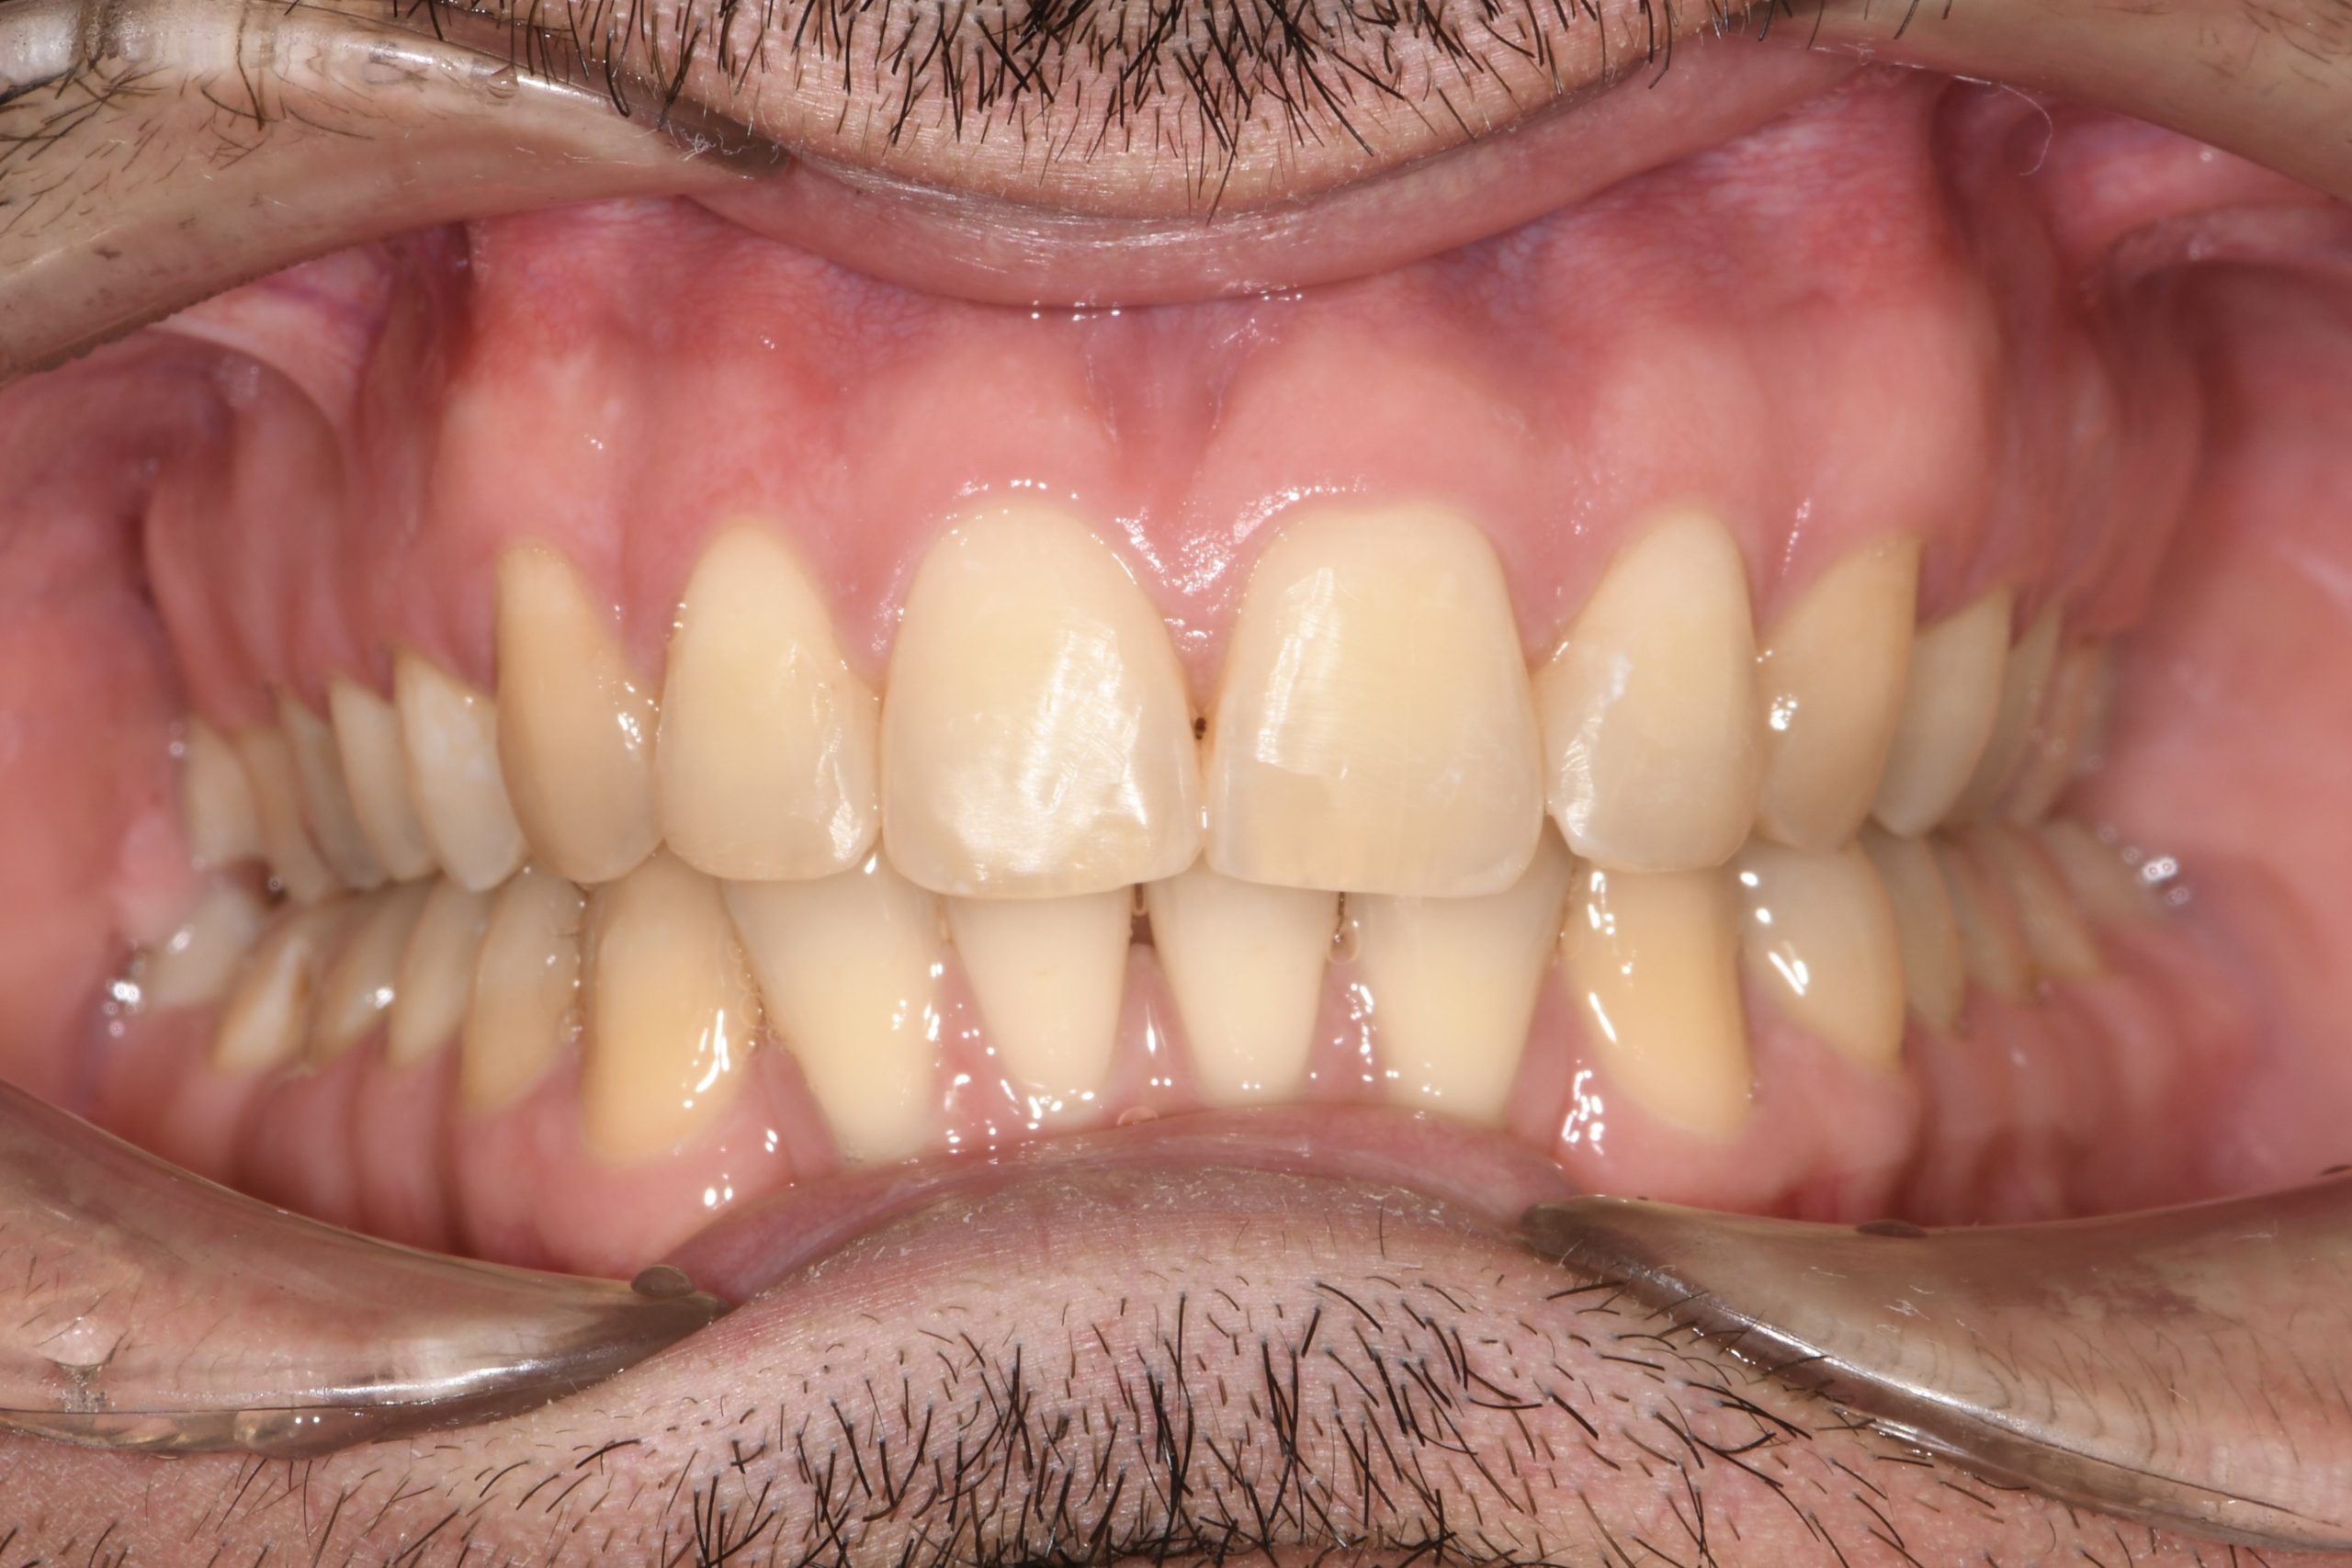

Az elmúlt évekből rengeteg szakmai referenciát tudnánk bemutatni, amelyek különböző fogszabályozási problémákat oldottak meg. Válogatva a több száz esetből, ezen az oldalon olyan képeket, információkat igyekeztünk bemutatni, amelyeknek a segítségével a jövőbeni pácienseinknek azt tudjuk üzenni: A Te fogsorod is lehet gyönyörű!

(Képeket a Pácienseink külön írásos beleegyezésével mutatjuk be!)